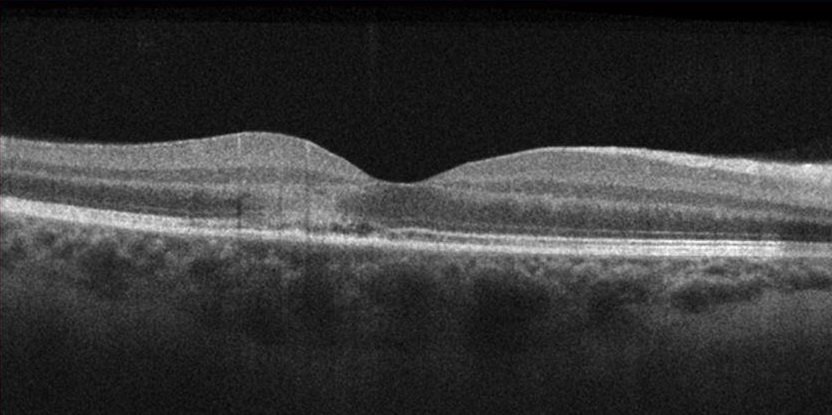

AMN in 22 year old female that presented with bilateral paracentral scotomas and blurry vision. Presenting BCVA was 20/20 OD and 20/25 OS.

Right eye: